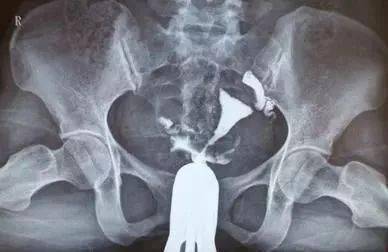

輸卵管造影是輸卵管粘連的一種檢查,做了輸卵管造影之后的女性,一定要遵循醫(yī)囑。

輸卵管造影后注意事項(xiàng):

1)造影前3天內(nèi)禁止性生活,及術(shù)后2周應(yīng)禁止性生活。

2)有時(shí)因輸卵管痙攣造成輸卵管不通的假象,必要時(shí)重復(fù)進(jìn)行。

3)如果有碘過(guò)敏,不可向醫(yī)生隱瞞碘過(guò)敏史,每次造影前必須做碘過(guò)敏試驗(yàn)。

4)造影時(shí)間應(yīng)在產(chǎn)后6個(gè)月,診刮及人流等宮腔操作手術(shù)后6周以后,正常月經(jīng)干凈后3-7天內(nèi)進(jìn)行。

5)造影檢查后一周內(nèi)有少量陰道出血如無(wú)其它不適屬正?,F(xiàn)象,如出血量較多超過(guò)月經(jīng)量或有其它不適應(yīng)該與你就診的醫(yī)生聯(lián)系。

6)造影檢查后最好避孕三個(gè)月,以減少X線照射有可能產(chǎn)生的的影響。但是臨床上觀察發(fā)現(xiàn)造影后當(dāng)月懷孕的女性,并沒(méi)有增加胎兒異常的危險(xiǎn)。